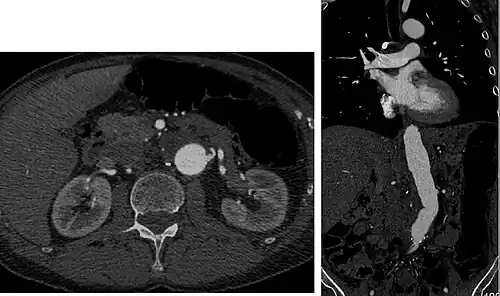

CT angiography (CTA) is highly effective for evaluation of the arterial system, and has largely replaced conventional angiography due to the lower risk profile and ability to survey the entire abdomen. Images are acquired after a rapid bolus of intravenous contrast material (3-7 cc/s) during the arterial phase (15–35 seconds after injection) when the concentration of contrast material in the arterial system is high (figures 3). Images are usually acquired using narrow collimation (<1 mm) and can be retrospectively reconstructed using dedicated 3-dimensional workstations and software. CTA is commonly used in the head and chest in the evaluation of pulmonary emboli, aneurysms, vascular malformations, dissection, bleeding and ischemia. Indications for early arterial phase imaging include: evaluation of aneurysms or dissections (cerebral, aortic, etc.), hepatic, splanchnic or renal arterial anatomy, and arterial imaging in liver or kidney transplantation. Single phase arterial imaging is often used in the evaluation of trauma patients either a complete chest/abdomen/pelvis examination with arterial phase imaging of the chest and portal venous phase imaging of the abdomen/pelvis or just a portal venous phase of abdomen and pelvis depending on the mechanism and severity of the trauma. CTA is also commonly performed in the abdomen and pelvis for evaluating vascular malformations and in the evaluation of bleeding. Mesenteric ischemia can also be evaluated using CT angiography. CTA of the abdomen and pelvis is often performed in combination with a CTA for evaluating the extremity vasculature.